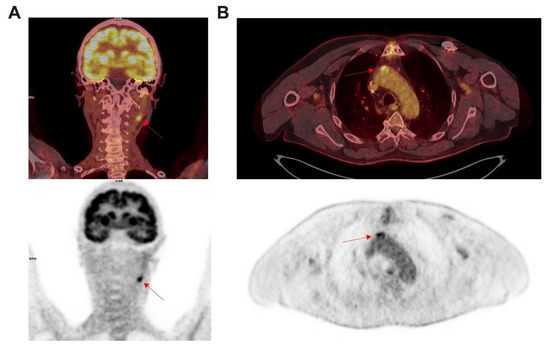

[18F]FDG PET/CT Imaging in Large Vessel Vasculitis